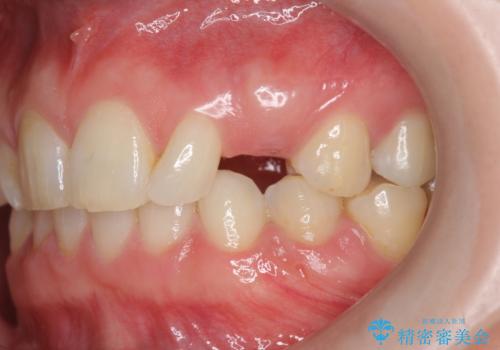

- 20代女性

- 欠損している前歯のインプラント治療を希望され来院されました。

前歯のインプラント治療は骨量・歯肉の厚み・インプラントの方向をしっかりと計画することで、審美的で長持ちを期待できるような仕上がりとなります。